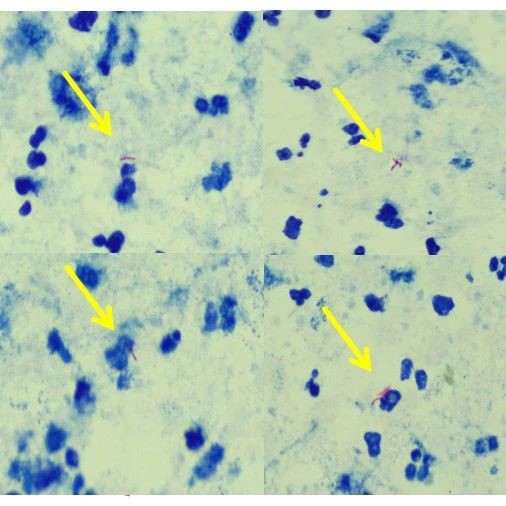

• 夺命的“蚊子病”-脑型疟疾